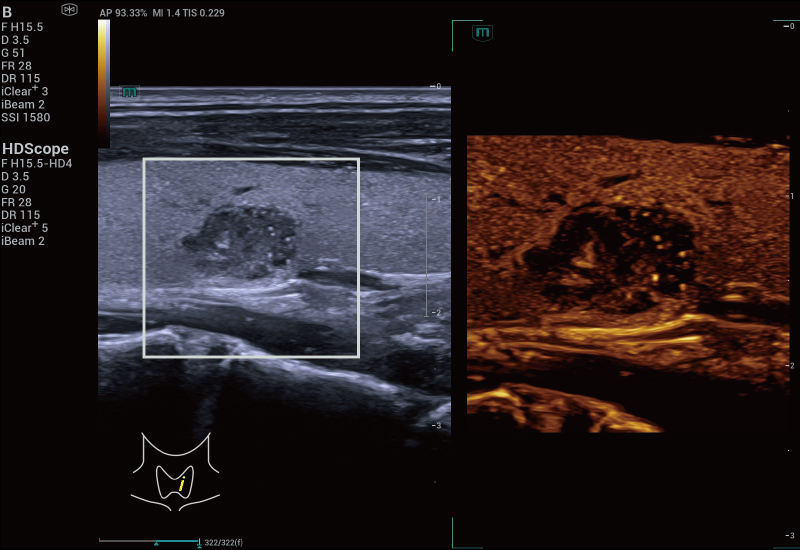

STVi maakt de kwantitatieve evaluatie van weefselviscositeit mogelijk en biedt realtime, multi-parametrische beeldvorming. Dit maakt een bredere benadering mogelijk van beeldvormingsdiagnose en kwantitatieve analyse van chronische leverziekten, borstlaesies en andere aandoeningen.

Beoordeling van borsttumoren